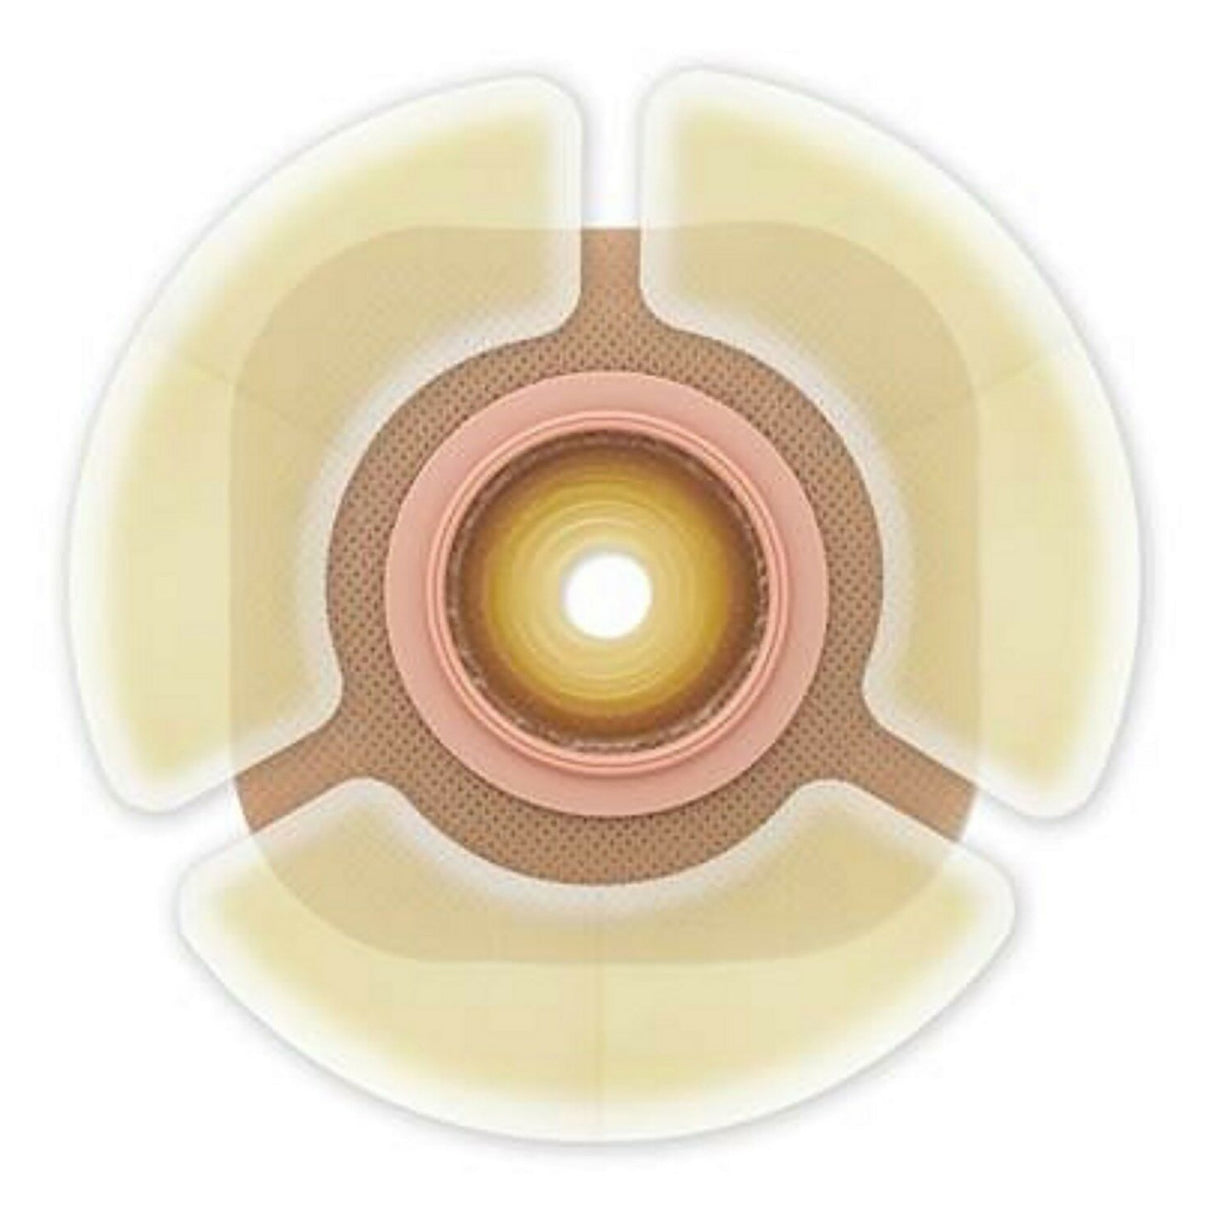

Skin Barrier Strip Ceraplus™

- Three piece configuration helps users to achieve a custom fit around the skin barrier

- Infused with ceramide-infused formula helps form a protective, waterproof barrier that helps keep skin healthy from Day 1

- CeraPlus™ Barrier Extenders are infused with ceramide to protect the skin and provide an added sense of security by framing the skin barrier with a thin, flexible, hydrocolloid adhesive.